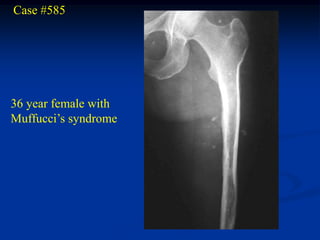

Case #585

36 year female with

Muffucci’s syndrome

Lateral view showing

phleboliths

Opposite femur

Lateral view with

hemangioma

enchondroma

Gross specimen